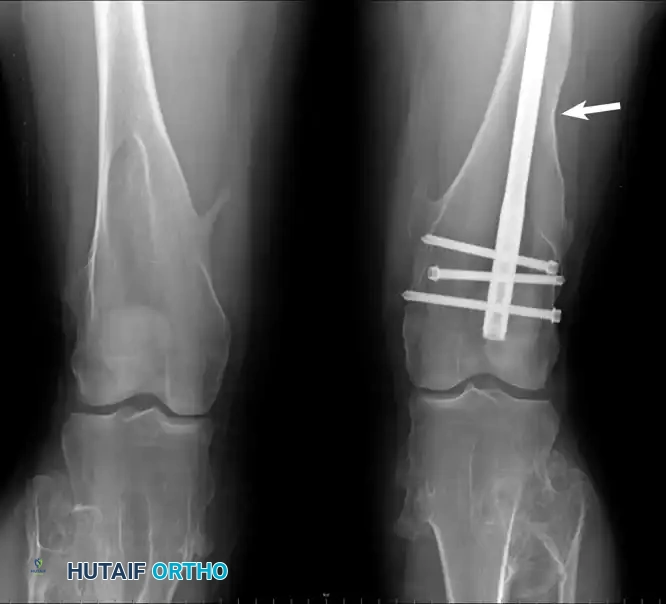

Clinical photograph and radiograph of the knees in a 22-year-old woman with multiple hereditary exostoses. Note the profound metaphyseal broadening, tibial angulation, and a healed femoral fracture sustained post-resection.

Patients with MHE present with numerous osteochondromas and associated profound disturbances in skeletal growth. These include abnormal tubulation of bones (producing broad, blunt, "Erlenmeyer flask" metaphyses), bowing of the radius, shortening of the ulna (leading to ulnar deviation of the hand), and valgus deformities of the knee and ankle. MHE occurs in approximately 1 in 50,000 individuals and is more frequently symptomatic than solitary lesions.